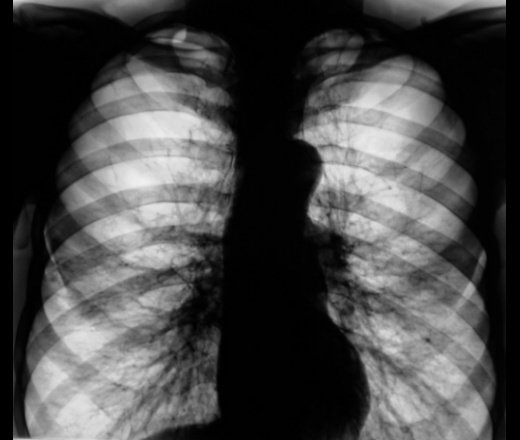

Хронический бронхит, резкое обеднение рисунка с двух сторон в верхних отделах - легочная дистрофия с ограниченной эмфиземой. Хроническое легочное сердце, артериальная гипертензия 2 степени. Возможны незаращение Баталлова протока или дефект межжелудочковой перегородки. Пневмонии не найдено

На гипоплазию в\долевой артерии, по крайней мере справа, очень даже смахивает....

"Агенезия и гипоплазия лёгочной артерии и её ветвей возникают изолированно или могут сочетаться с гипоплазией лёгкого или пороками сердца. Порок развития рентгенологически характеризуется сужением и повышением прозрачности лёгочного поля, обеднением и дезорганизацией лёгочного рисунка. На сцинтипневмограммах выявляют отсутствие или нарушение лёгочного кровотока. На ангиопульмонограммах - отсутствие или редукцию сосудов системы лёгочной артерии."

..., а также "дебилизм наших коллег - клиницистов". Каждый год этот пациент направляется ко мне терапевтами с диагнозом "двустороняя пневмония". В 2009 году мне это рукоблудство надоело (а пациент, умело пользуется имеющейся "патологией") и я настоял на производстве КТ. КТ (с контрастированием) выдало гипоплазию ветвей легочной артерии. Кажется все, точка. Но не тут-то было, аускультантам, что-то опять не понравилось..., а вдруг... и они вновь направили...

На снимке (качество - не для оценки сосудов лёгких) "кричит" перегруженное "порочное" сердце, присутствует и ЛГ (стадию не скажу - не ставлю в принципе), в плане венозного застоя - возможно, что есть (о чём упоминал - срыв компенсат. механизмов), но непоказателен: превалирует сердечная патология (снимок "по режиму" - на сердце)!..